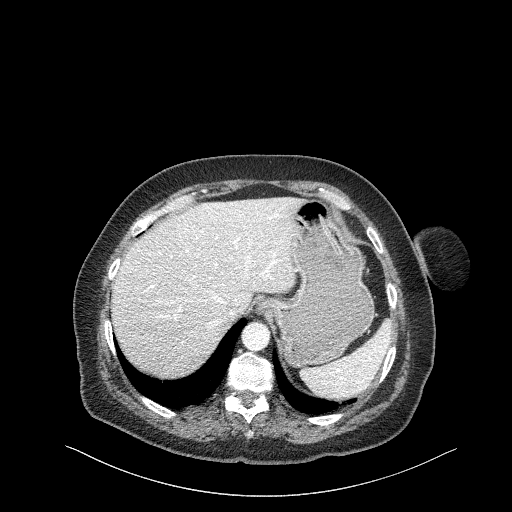

Original NATIVE CT scan (input)

Full window (WL 1023.5, WW 4095 β†’ Low βˆ’1024, High +3071)

Lung window (WL -600, WW 1500 β†’ Low βˆ’1350, High +150)

Mediastinum window (WL 40, WW 400 β†’ Low βˆ’160, High +240)